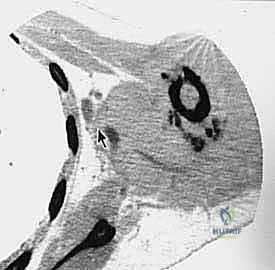

- التصوير الطبي المتقدم: استخدام الرنين المغناطيسي (MRI) لتقييم الأنسجة الرخوة، والأشعة المقطعية (CT scan) للصدر للبحث عن أي نقائل سرطانية (Metastasis)، والتصوير المقطعي بالإصدار البوزيتروني (PET Scan).

الخطوة 3: التعامل مع عظم الترقوة (Clavicle Osteotomy)

يتم كشف عظم الترقوة وقصه (قطعه) من المنتصف أو بالقرب من مفصل القص. هذه الخطوة "تفتح الباب" للوصول إلى الهياكل الحيوية العميقة.